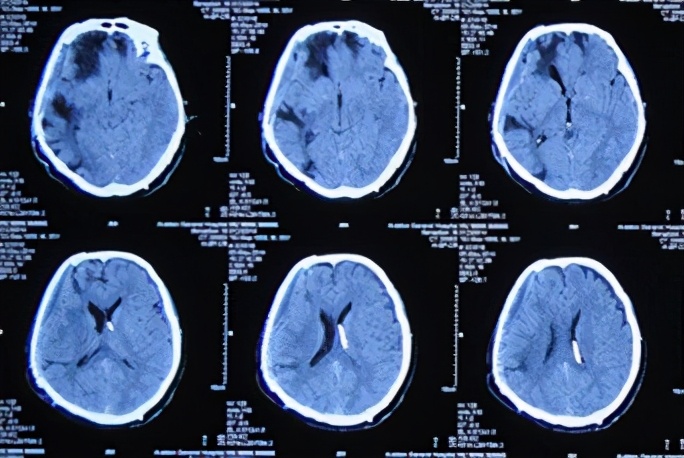

患者于2013年9月17日凌晨因车祸致头部外伤、昏迷,急诊于山东省聊城市某医院就诊,头CT检查发现双额及右颞叶多发脑挫裂伤并右侧脑室受压、中线左移(图-1),当天进行了右侧额颞叶脑挫裂伤血肿清除并去骨瓣减压术,术后头CT:去骨瓣减压术后状态(图-2)。

图-1:2013年9月17日术前头CT

图-2:2013年9月17日术后头CT